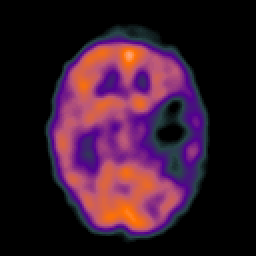

Metastatic bronchogenic carcinoma, overlay -- Slice #8

[Home][Help][Clinical] Slice 8